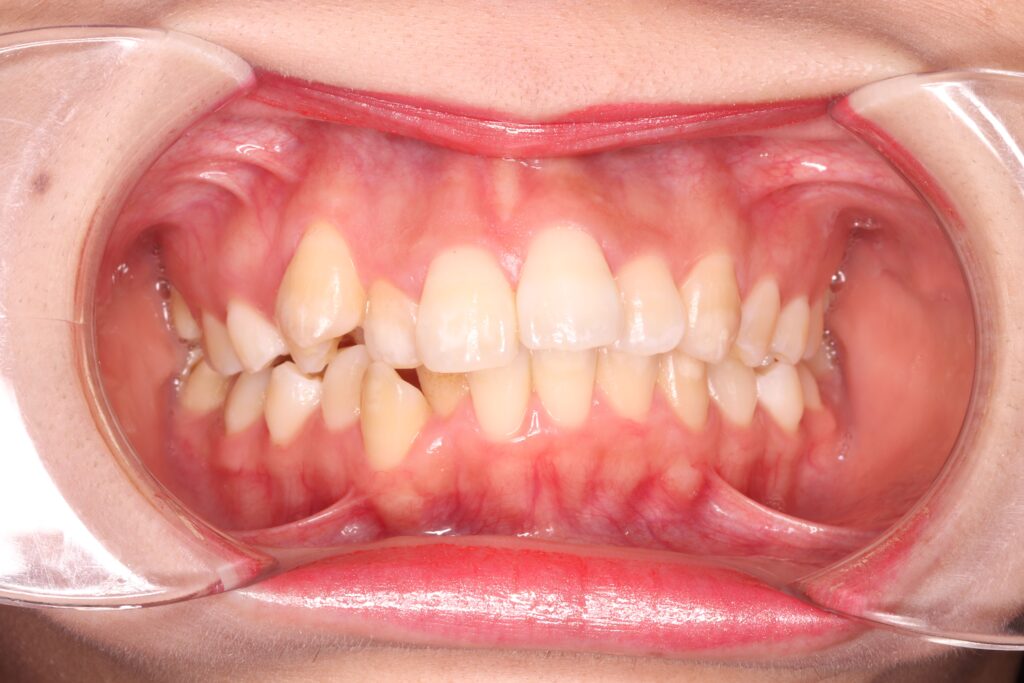

私は元々歯並びのガタつき、出っ歯が気になっており、このような状態でした😢

【当初の歯並び】

一度は矯正治療を検討していましたが、当時は学生だったこともあり、費用を安く抑えたい、とりあえず見た目が改善されればいいか、と考え『部分矯正』を選択してしまいました。

部分矯正は全体矯正と比較すると安価であったり、治療期間が短い点が魅力とされていますが、上下の前歯6本ずつのみを動かしていく方法だった為、噛み合わせや、出っ歯の改善はできませんでした。